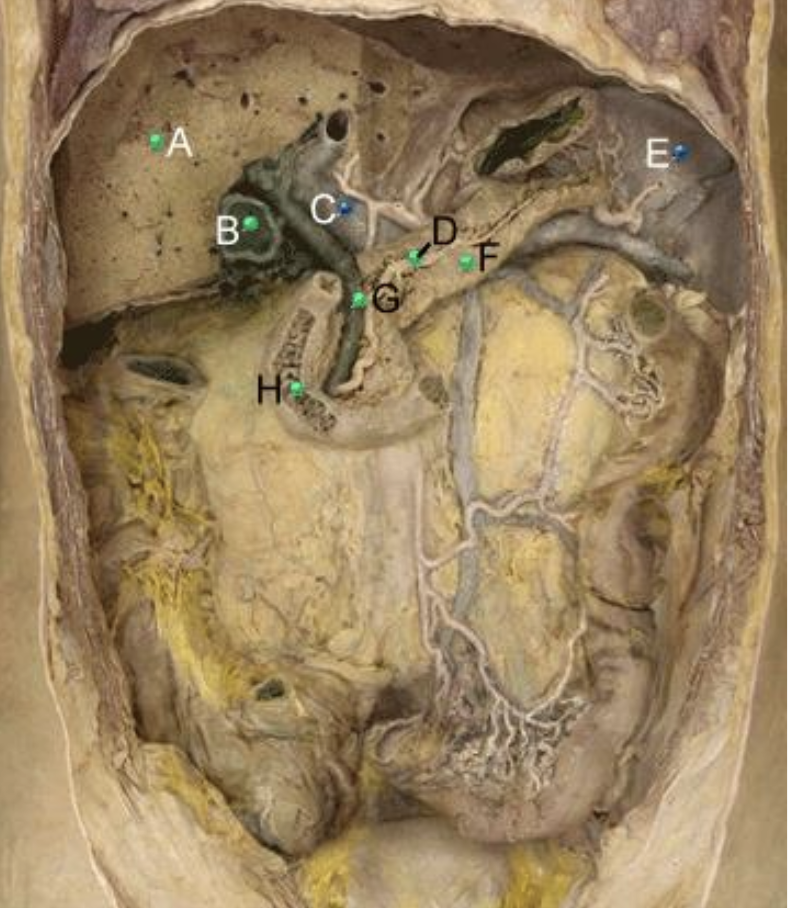

Part A?

stomach

Part B?

Spleen

Part C?

Splenic artery

Part D?

Part E?

body of pancreas

part F?

Duodenum

Part G?

inferior mesenteric vein and tributaries

Part H?

ascending colon

Part I?

abdominal aorta

Part J?

inferior mesenteric artery and branches

Part K?

descending colon

Part L?

lleum

Part M?

taeniae coli

Part N?

sigmoid colon

Part O?

cecum

Part P?

urinary bladder with peritoneum